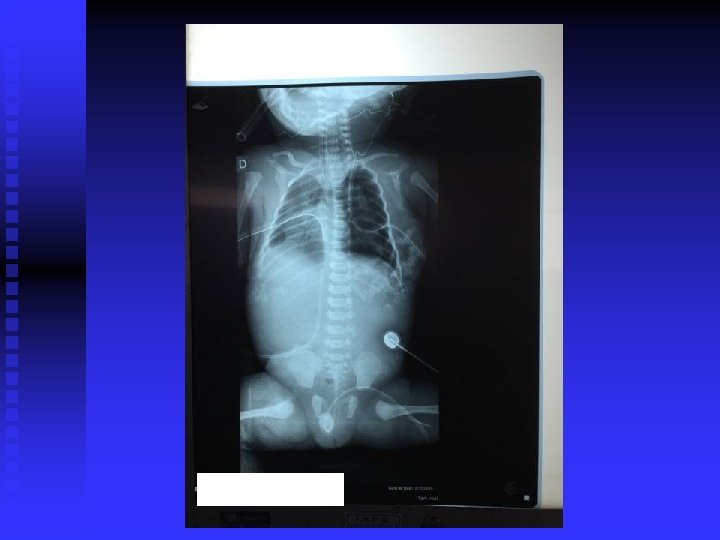

n Conduta: n VM (A/C): PIP: 18, PEEPp: 6, 5 Fi. O 2: 80% FR: 44 Ti: 0, 4 n Dieta zero + SOG + cateterismo venoso umbilical. n Fentanil + P. Cristalina e Gentamicina n RX de tórax: derrame volumoso à direita e pequeno à esquerda. Coração de tamanho reduzido. n CIPE: drenagem de tórax à direita (líquido citrino em grande quantidade).

n ECO (05/10/15): Hipertensão pulmonar moderada. Insuficiência Tricúspede moderada. Derrame pericárdio discreto. Derrame pleural bilateral maior à esquerda. FOP. n CIPE: drenagem de tórax à D (líquido citrino: 260 ml) n Rx de tórax: - Coração desviado para a D. - Derrame somente de seio costofrênico à D. - Derrame pleural em todo HTE.

n Rx de tórax: pulmões com expansibilidade assimétrica. Mediastino desviado para a D. Pulmão E: hiperexpandido e hiperinsulflado. Pulmão D: praticamente colabado. Dreno de tórax à D muito introduzido. Derrame refazendo à direita com apagamento de seio costofrênico D. n Tracionado dreno de tórax a direita ( 2 cm )